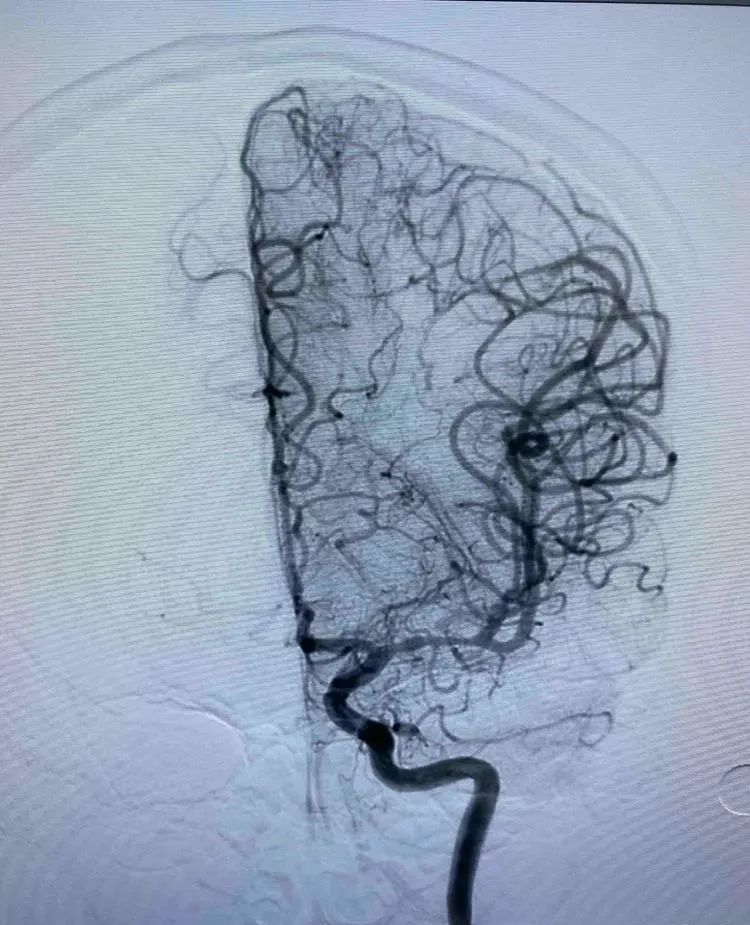

治疗过程